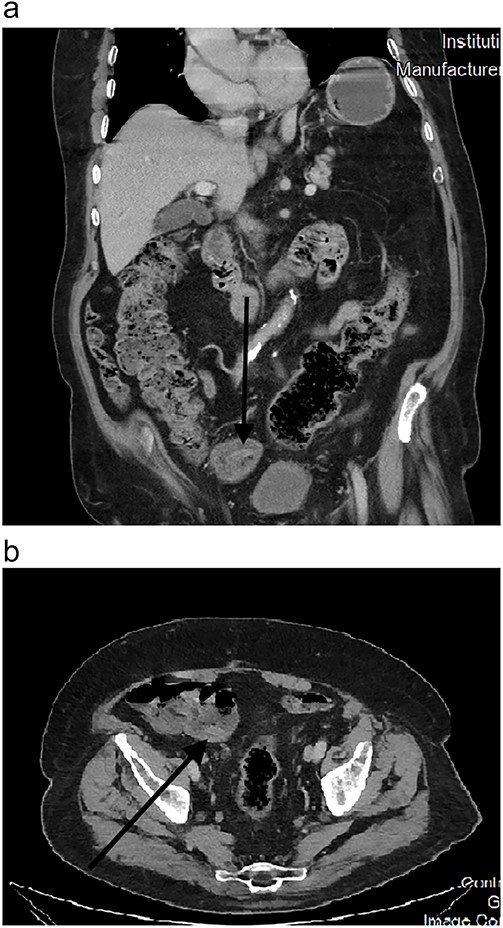

CT scans also picked up this anomaly as early as 2010 (Fig. 2). Further scans in the following years showed no change in morphology (Fig. 3a and b), and it was kept under surveillance. To note, our patient did not have any abdominal symptoms suggestive of appendiceal origin throughout the years.

Endoscopically, it appears as a tubular elongated polypoid structure arising from the appendiceal orifice [11, 12]. Endoscopists can be reluctant to rule out neoplastic findings without a histological confirmation (such was the case in our patient’s 2012 colonoscopy). On CT scans, it appears as an elongated structure with a layered appearance at the appendiceal orifice. The presence of feces in the cecum might make diagnosis difficult [13].

Appendiceal intussusception is classified according to the McSwain classification: Type 1: tip of the appendix invaginates into the appendiceal lumen. Type 2: extension of type 1 where there is more pronounced invagination beyond the tip of the appendix. Type 3: the appendix intussuscepts all the way to the appendiceal orifice at the caecum, which is the most common type. Type 4: retrograde inversion of the proximal appendix distally toward the tip. Type 5: complete invagination of the appendix through the orifice into the cecum [13]. Our case is classified as Type V.